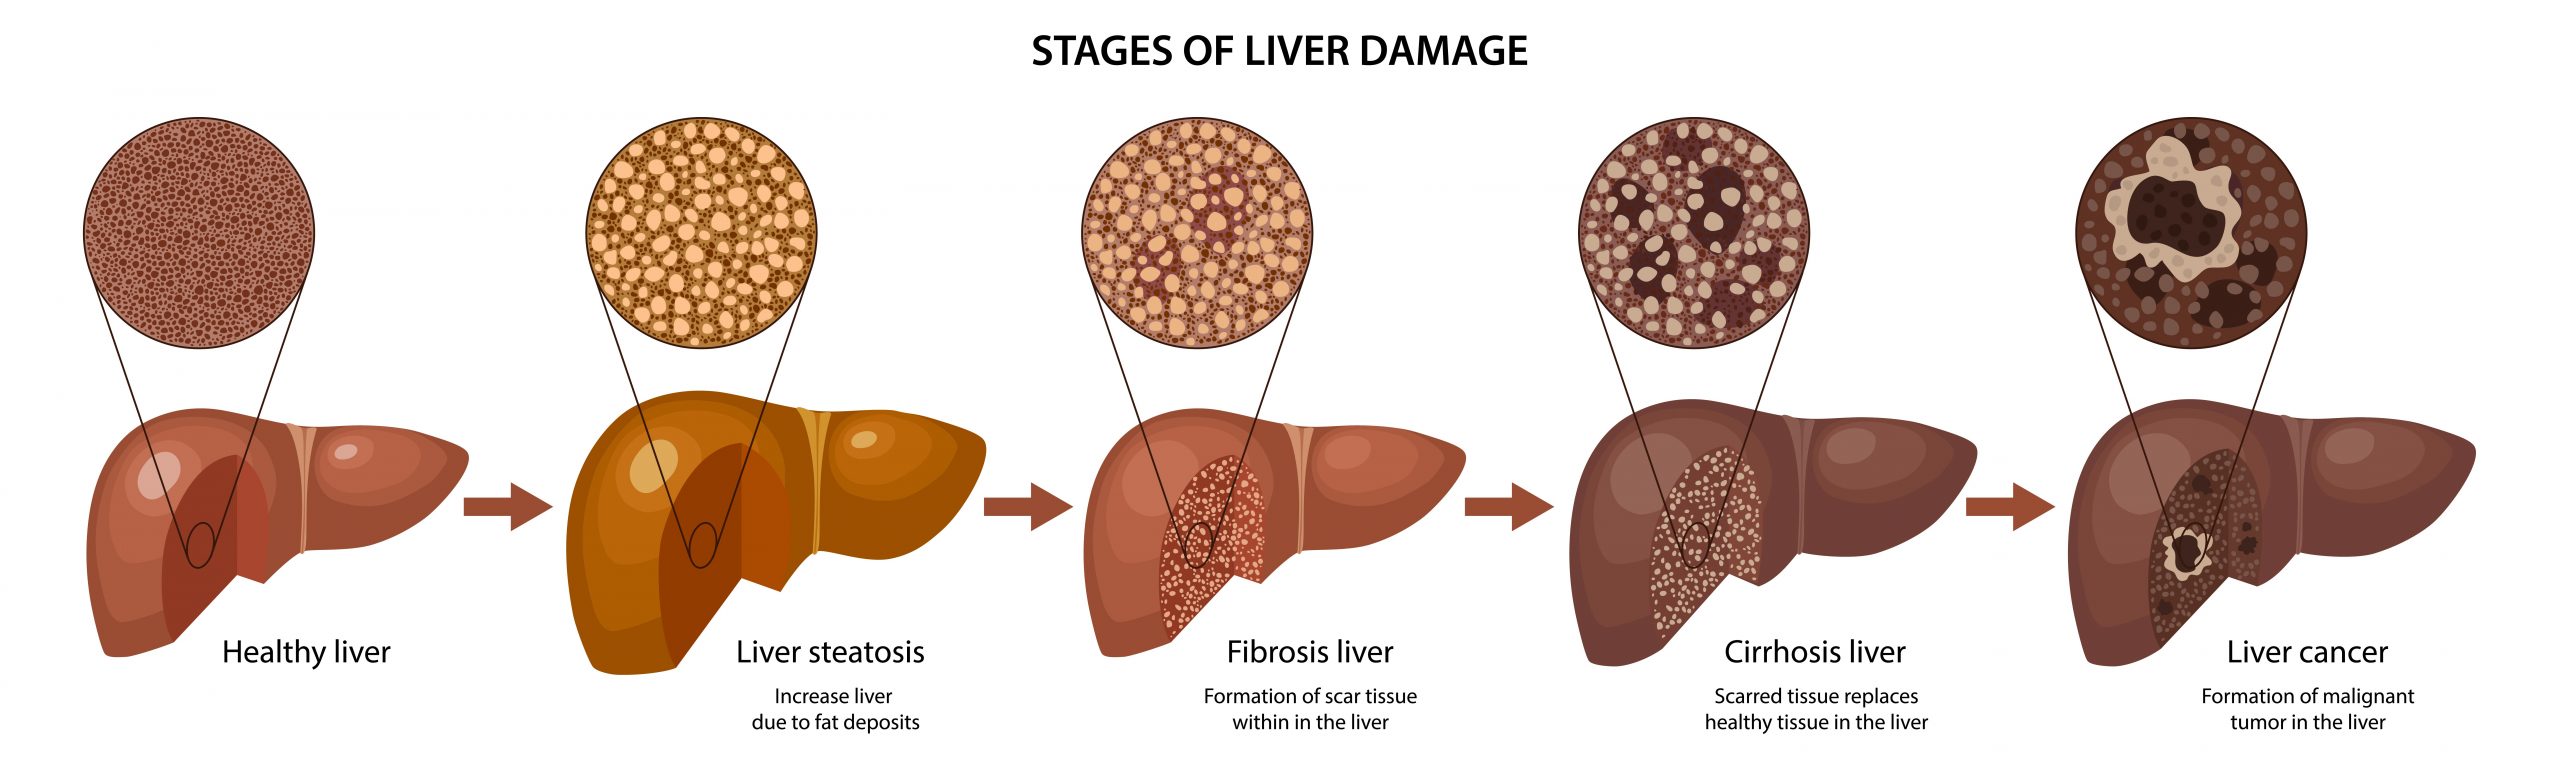

It is thought eight percent of the Japanese adult population and up to 12 percent of the adults in the US have NASH, a condition that causes patients to develop a fatty liver regardless of alcohol consumption. In more advanced stages NASH can cause liver cirrhosis and cancer. NASH symptoms include liver tissue inflammation, fat deposition and fibrosis. There are currently no medications available for treating NASH.

The early (fatty liver), middle (fatty liver) and advanced (advanced fibroids) stage organoids were histologically examined using stains: HE staining to visualise cell shapes, oil red staining to show oil production and Masson’s trichrome staining to highlight connective tissues. The team also used immuno-staining, quantitative PCR and RNA-sequencing to examine expression and localisation of biomarkers.

A comparison of the organoids to human NASH liver samples revealed they had similar characteristics at the three stages.